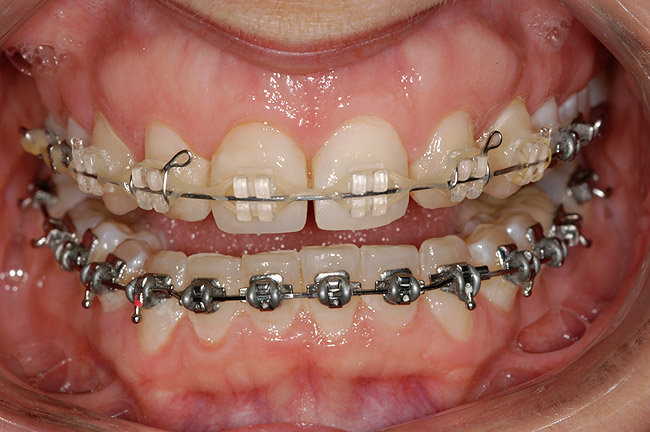

Figure 3 Additional orthodontic treatment is initiated to improve the dental midline and evenly distribute the space around the microdontic lateral incisors.

Figure 3

Figure 4 The dental midline is in improved harmony with the facial midline following the second round of orthodontic treatment.

Figure 4